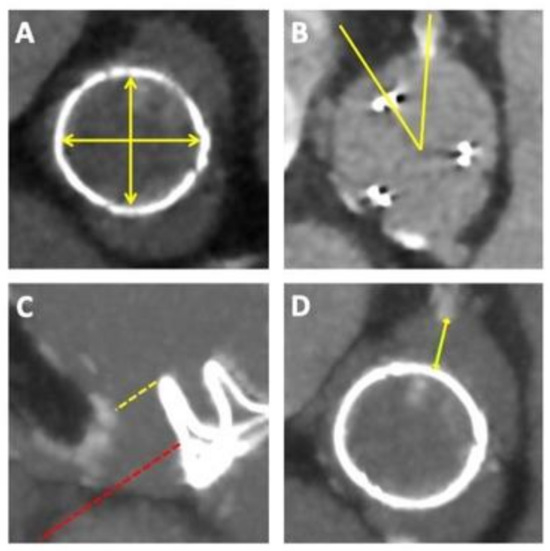

Figure 2.

Pre-procedural planning for ViV-TAVI. Pre-procedural computed tomography is required to evaluate the (A) true internal dimensions of the implanted SAV, (B) the alignment of the SAV with respects to the native coronaries, (C) the coronary and sinus heights in relation to the top of the SAV frame, or if no posts are visible, then anticipated heights of leaflets and (D) the gap between the frame and/or leaflets and coronary ostia to estimate the risk for coronary obstruction.